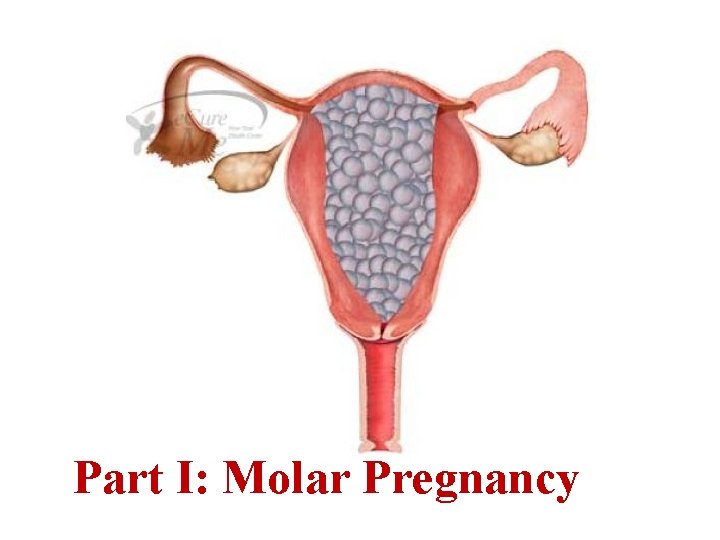

Part I: Molar Pregnancy

Hydatidiform Moles (H. M. ) Hydatidiform moles are abnormal pregnancies characterized histologically by : Ø Trophoblastic proliferation & Ø Edema of the villous stroma (Hydropic). Based on the degree and extent of these tissue changes, hydatidiform moles are categorized as either Complete hydatidiform mole. Partial hydatidiform mole.